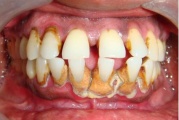

Krooniline parodontiit

Krooniline parodontiit on mikroobide poolt põhjustatud hammaste tugikudede põletik, mille tulemusena tekib progresseeruv alveolaarluu (nähtav röntgenograamil) ja periodontaalligamendi destruktsioon, igemetaskute moodustumine, igeme retsessioon või mõlemad kahjustused kombineeritult. Loe edasi »

- igemepiir on taandunud (3)

- luu destruktsioon (5)

- hammaste asukoha muutus (5)

- vahed hammaste vahel (5)

- igemetaskust eritub mäda (3)

- parodontaalne abstsess (2)